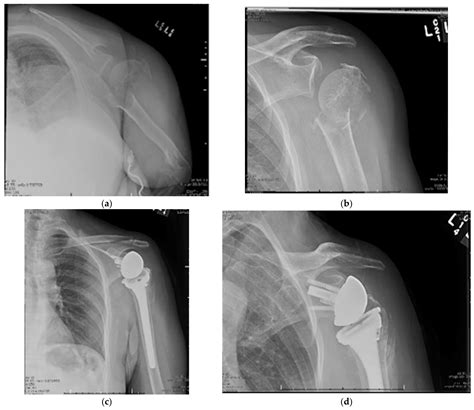

For more severe fractures, surgery may be necessary to realign the bone and promote healing. Surgical options include:

• Open Reduction and Internal Fixation (ORIF): A procedure where the fracture is surgically realigned and stabilized using plates, screws, or pins.

• Hemiarthroplasty: Replacement of the humeral head with a prosthetic component, often used in older adults with severe fractures.

• Reverse Total Shoulder Arthroplasty: A more complex procedure where both the humeral head and the glenoid (socket) are replaced, providing better stability and function.

Case Study 3: Ms. Lee, 30 Years Old

Ms. Lee, a 30-year-old athlete, sustained a proximal humerus fracture during a skiing accident. Her fracture was classified as a three-part fracture, and she underwent reverse total shoulder arthroplasty. She underwent intensive physical therapy and made a full recovery, returning to her athletic activities within a year.